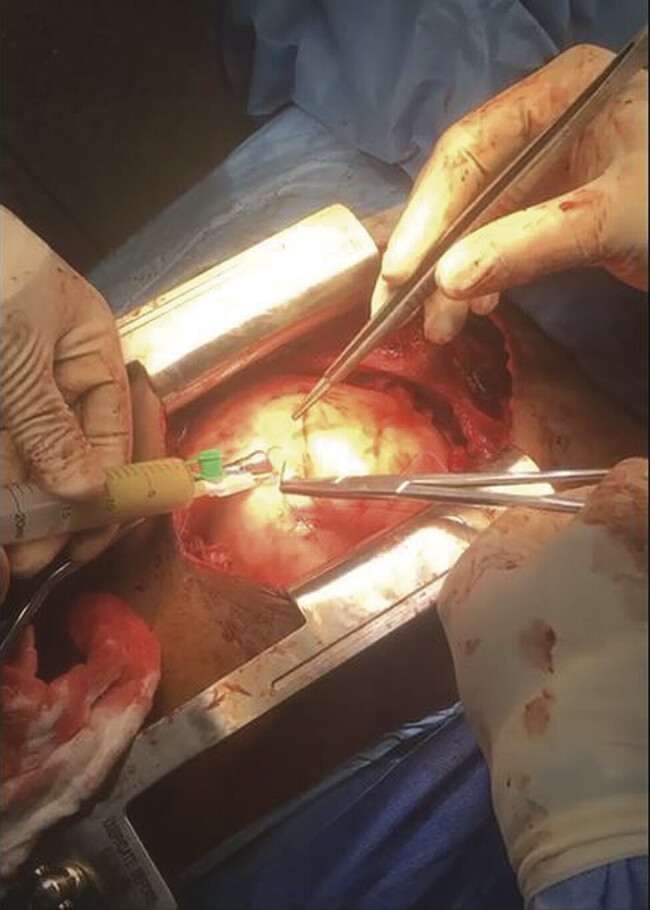

胸膜心包囊肿是一种罕见的纵隔肿瘤,临床表现多变,常为严重的儿童,偶尔需要紧急干预。我们报告的情况下,以前健康的14岁男性谁是入院严重充血性心力衰竭的迹象和心脏填塞的临床证据。经胸超声心动图和胸部CT扫描证实存在压缩纵隔囊性肿块。患者经胸骨正中切开术行紧急手术切除。组织病理学检查证实为良性心包囊肿。术后恢复平稳,随访2年无复发。

Pleuropericardial cysts are rare mediastinal tumors with variable, often severe, clinical presentations in children, occasionally requiring urgent intervention. We report the case of a previously healthy 14-year-old male who was admitted with signs of severe congestive heart failure and clinical evidence of cardiac tamponade. Transthoracic echocardiography and thoracic CT scan confirmed the presence of a compressive mediastinal cystic mass. The patient underwent emergency surgical resection via median sternotomy. Histopathological examination confirmed a benign pericardial cyst. Postoperative recovery was uneventful, and no recurrence was observed after 2 years of follow-up.